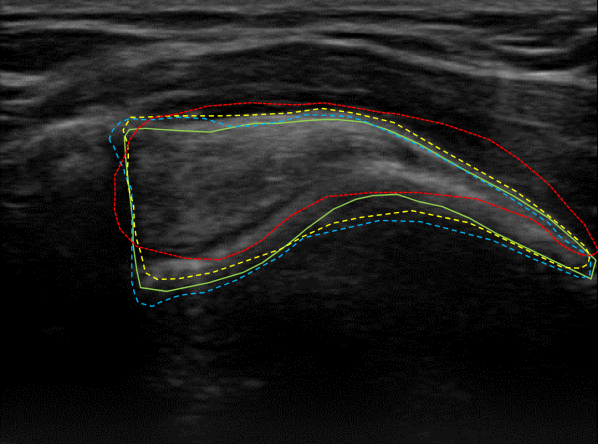

Qualitative performance and advantage of our proposed segmentation method over two different methods are presented in Fig. 8. In this figure, original US images of three cases taken from the SST data-set are shown in the first row and the second row depicts the raw predictions of the NASUNet model. On each image, boundaries of the segmentation maps derived from the ground truth (radiologist annotation), proposed method (NASUNet), DeepLab V3 network (the second best performing method in Table 1), and Active Appearance Model (AAM, the worst-performing method based on Table 1) are drawn with green, blue, yellow, and red colors, respectively. It is evident from Fig. 8 that the delineation by our method is closer to the ground truth annotation in comparison with other methods, which indicates the power and efficiency of NASUNet in SST boundary detection. In all of the subsequent tendinopathy recognition experiments, resulting segmentations from the best performing model (NASUNet) are utilized.

Figure 8: Visualizing the SST boundaries resulted from different segmentation methods for three different cases in the first row. Boundaries of ground truth, proposed NASUNet model, DeepLab v3 network, and AAM method are overlaid on their related images with green, blue, yellow, and red colors, respectively. The second row illustrates the raw segmentation prediction maps from NASUNet.